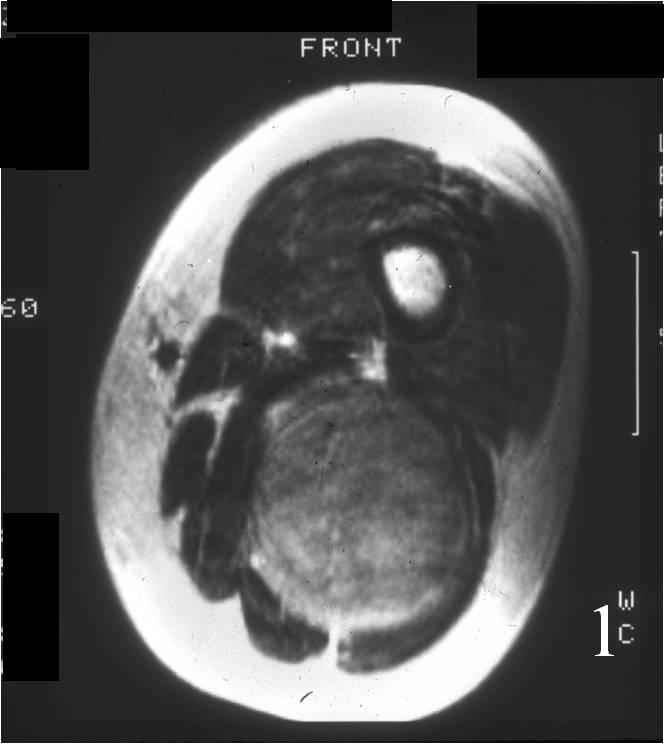

• • The work-up for neurofibroma often consists of a physical examination, X-ray, MRI, CT, and bone scans. The diagnosis is often confirmed with a biopsy, which samples the tumor for further analysis.

Radiographic imaging is used to help form a diagnosis of neurofibroma. These include X-Ray, MRI, CT and Bone Scans